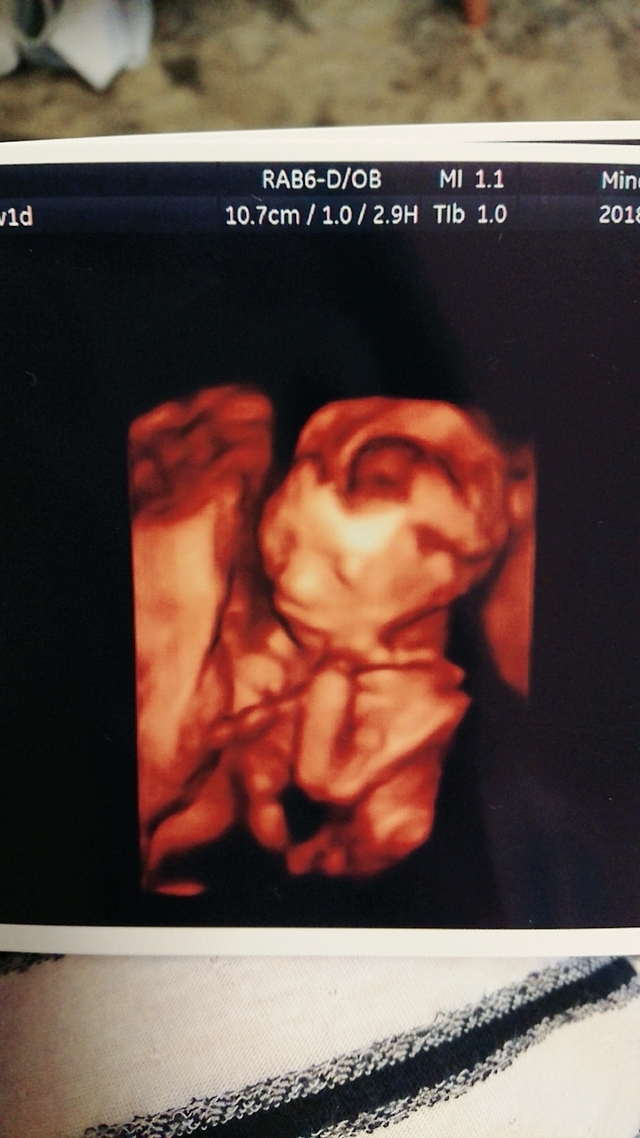

20週5日(20w5d・男の子)|あぁこ さん(31歳)

このエコー写真は検診に行き始めてから初めての立体的な写真です。この時点で男の子というのは確定だったのですが、顔立ちがしっかりしていて男前だなと思ってしまいました。(とても親バカ(笑)です)

エコーではいろんな角度から見せてもらえたりしてすごいなぁ…と感心しまくりでした。仕事もしていたので日に日に大きくなる我が子に喜びを感じている反面お腹が重たく体力的にもしんどかった記憶があります。

早産の危険もありましたが無事に産まれて来てくれて顔を見た時はエコー写真の面影があったので笑ってしまいました(*´-`)